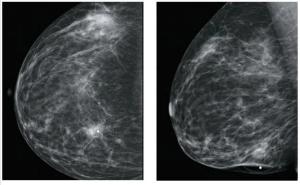

An asymptomatic 45-year-old woman presented for a screening mammogram and was noted to have a soft-tissue opacity with calcifications in the left breast. Ultrasound revealed a highly suspicious mass.